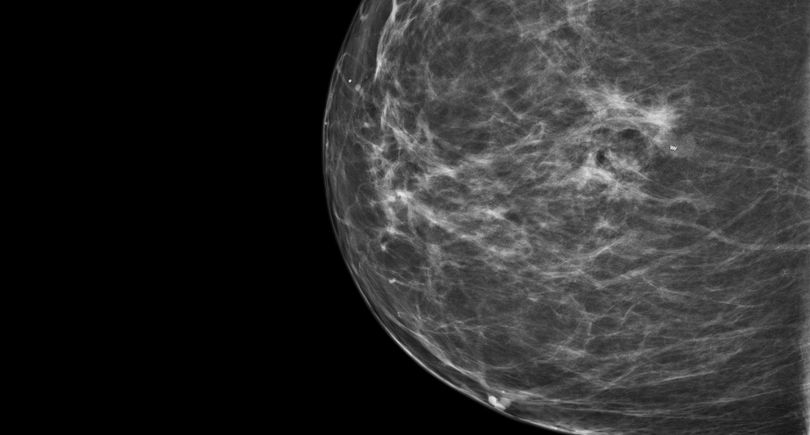

CESM is an advanced form of mammography that uses a safe dye injected into the bloodstream. This dye highlights areas of concern within the breast, giving clinicians a much clearer and more detailed image than a traditional mammogram.

“Sometimes it can be difficult to interpret a mammogram, especially in patients with dense breast tissue”, Nicole explains. “It’s a bit like looking for a cloud in a sky full of clouds. The contrast helps remove that ‘noise’ and shows us exactly what’s going on inside the breast.”

One of the biggest advantages of CESM is that it can be carried out during the patient’s breast clinic appointment and reviewed by a radiologist straight away. Before CESM was introduced, patients with unclear mammogram results often faced a longer wait for further tests, such as an MRI scan, to gather more information.

Breast Unit Consultant Shama Puri explains the impact CESM has had within the department so far: “CESM has enhanced patient care by providing us more accurate information and increasing the sensitivity for detecting breast cancers, especially in dense breasts. It is providing us with functional information similar to MRI but at lower cost and easy accessibility within the breast clinic leading to faster diagnosis and avoiding treatment delays. Thank you to Derby & Burton Hospitals Charity and their supporters for funding this technology.”